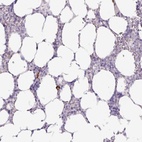

Immunohistochemical staining of human bone marrow shows cytoplasmic positivity in hematopoietic cells.